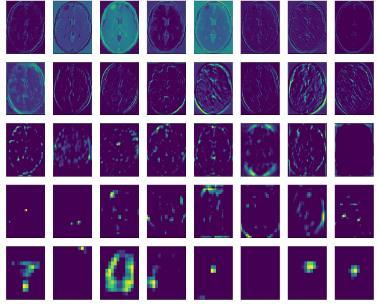

Maps Extracted from Final in

Modelis0.62857.

In figure 6 we can see that the result of applying the filters in the first convolutional layer is a lot of versions of the MRI image with different features highlighted. This is an interesting result and generally matches our expectation. We could updatetheexampletoplotthefeaturemapsfromtheoutputofotherspecificconvolutionallayers.